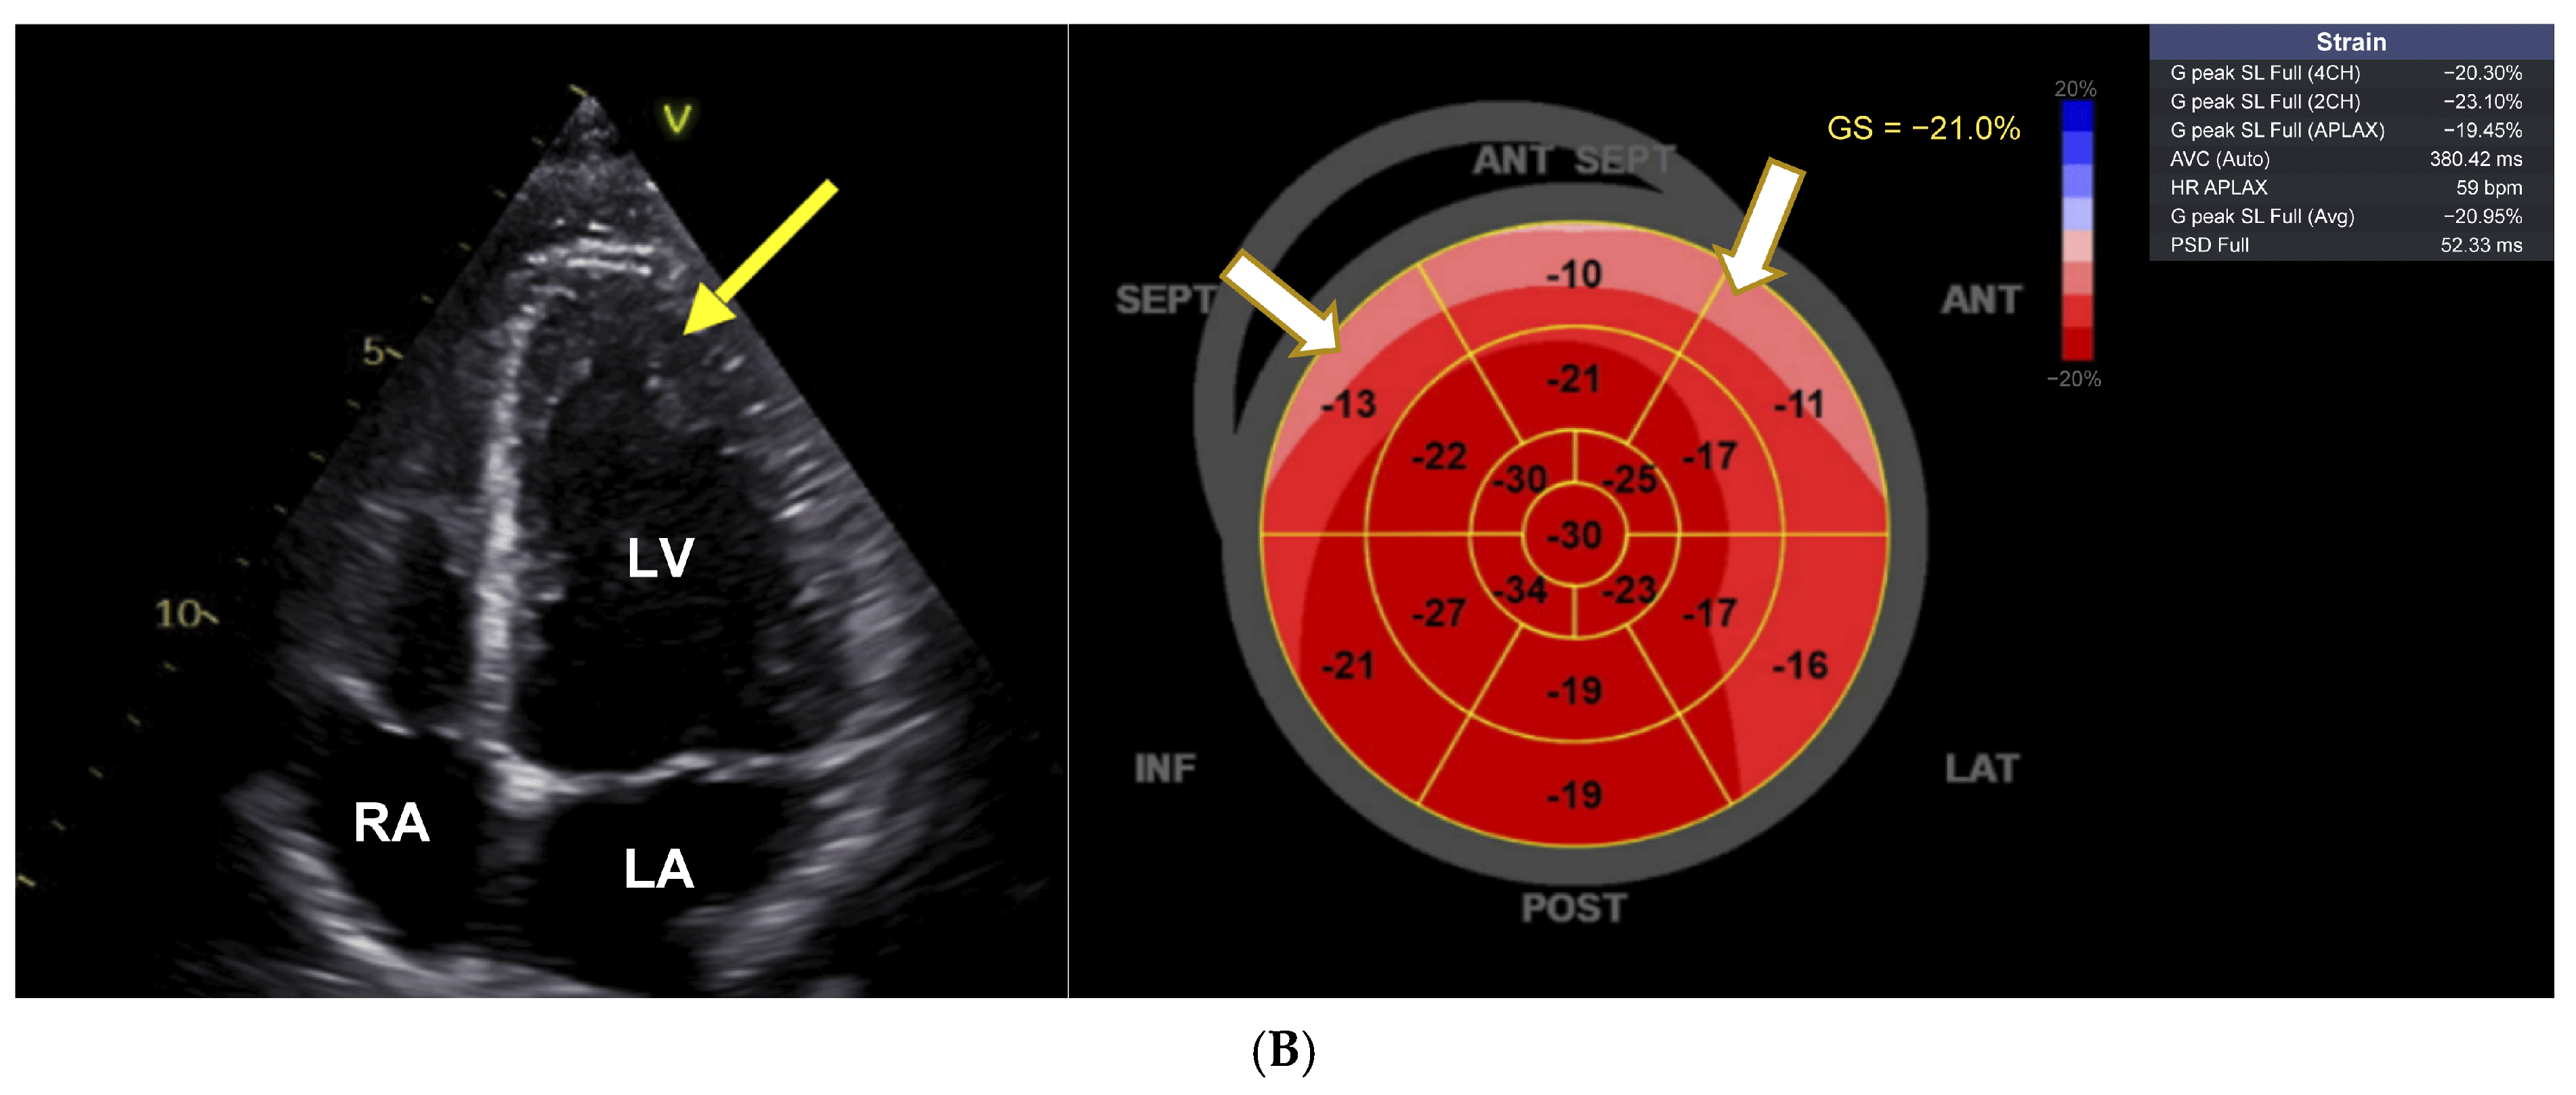

There was normal systolic and diastolic function, normal renin, aldosterone, adrenalin, and noradrenaline levels measured in serum, methoxytyramine was massively elevated (309 nmol/mL, normal range 0.59–4.19), and MRI showed no kidney or adrenal abnormalities. Echocardiography revealed signs of apical hypertrophic cardiomyopathy and decrease in global longitudinal strain (GLS) to −15.9% (Figure 1A). VEN serum concentration was not determined. VEN-associated CTOX was suspected and her migraine treatment switched from VEN to fremanezumab. Subsequently, within one year, the patient showed almost normal blood pressure values, normalization of ECG changes, and an increase in GLS to −21%. The echocardiographic signs of left ventricular hypertrophy had regressed (Figure 1B), and blood pressure had decreased to 143/84 mmHg. She had no dyspnea anymore, and her methoxytyramine levels had completely normalized.

Figure 1.

Pronounced cardiac anomaly showing features of hypertrophic cardiomyopathy. (A) Echocardiographic changes with apical hypertrophy and apical sparing pattern with decrease in strain in basal segments (white arrows). LA = left atrium, LV = left ventricle, RA = right atrium; white arrow points to left ventricular hypertrophy. Average GLS as shown on the right side is diminished and shows apical sparing (white arrows). (B) Reversal of left ventricular hypertrophy and apical sparing pattern after dose reduction of venlafaxine. LA = left atrium, LV = left ventricle, RA = right atrium; yellow arrow points to left ventricular hypertrophy. Average GLS as shown on the right side has now almost completely normalized (−21.9%), with some remaining decrease in basal septal, anteroseptal, and anterior segments (white arrows).